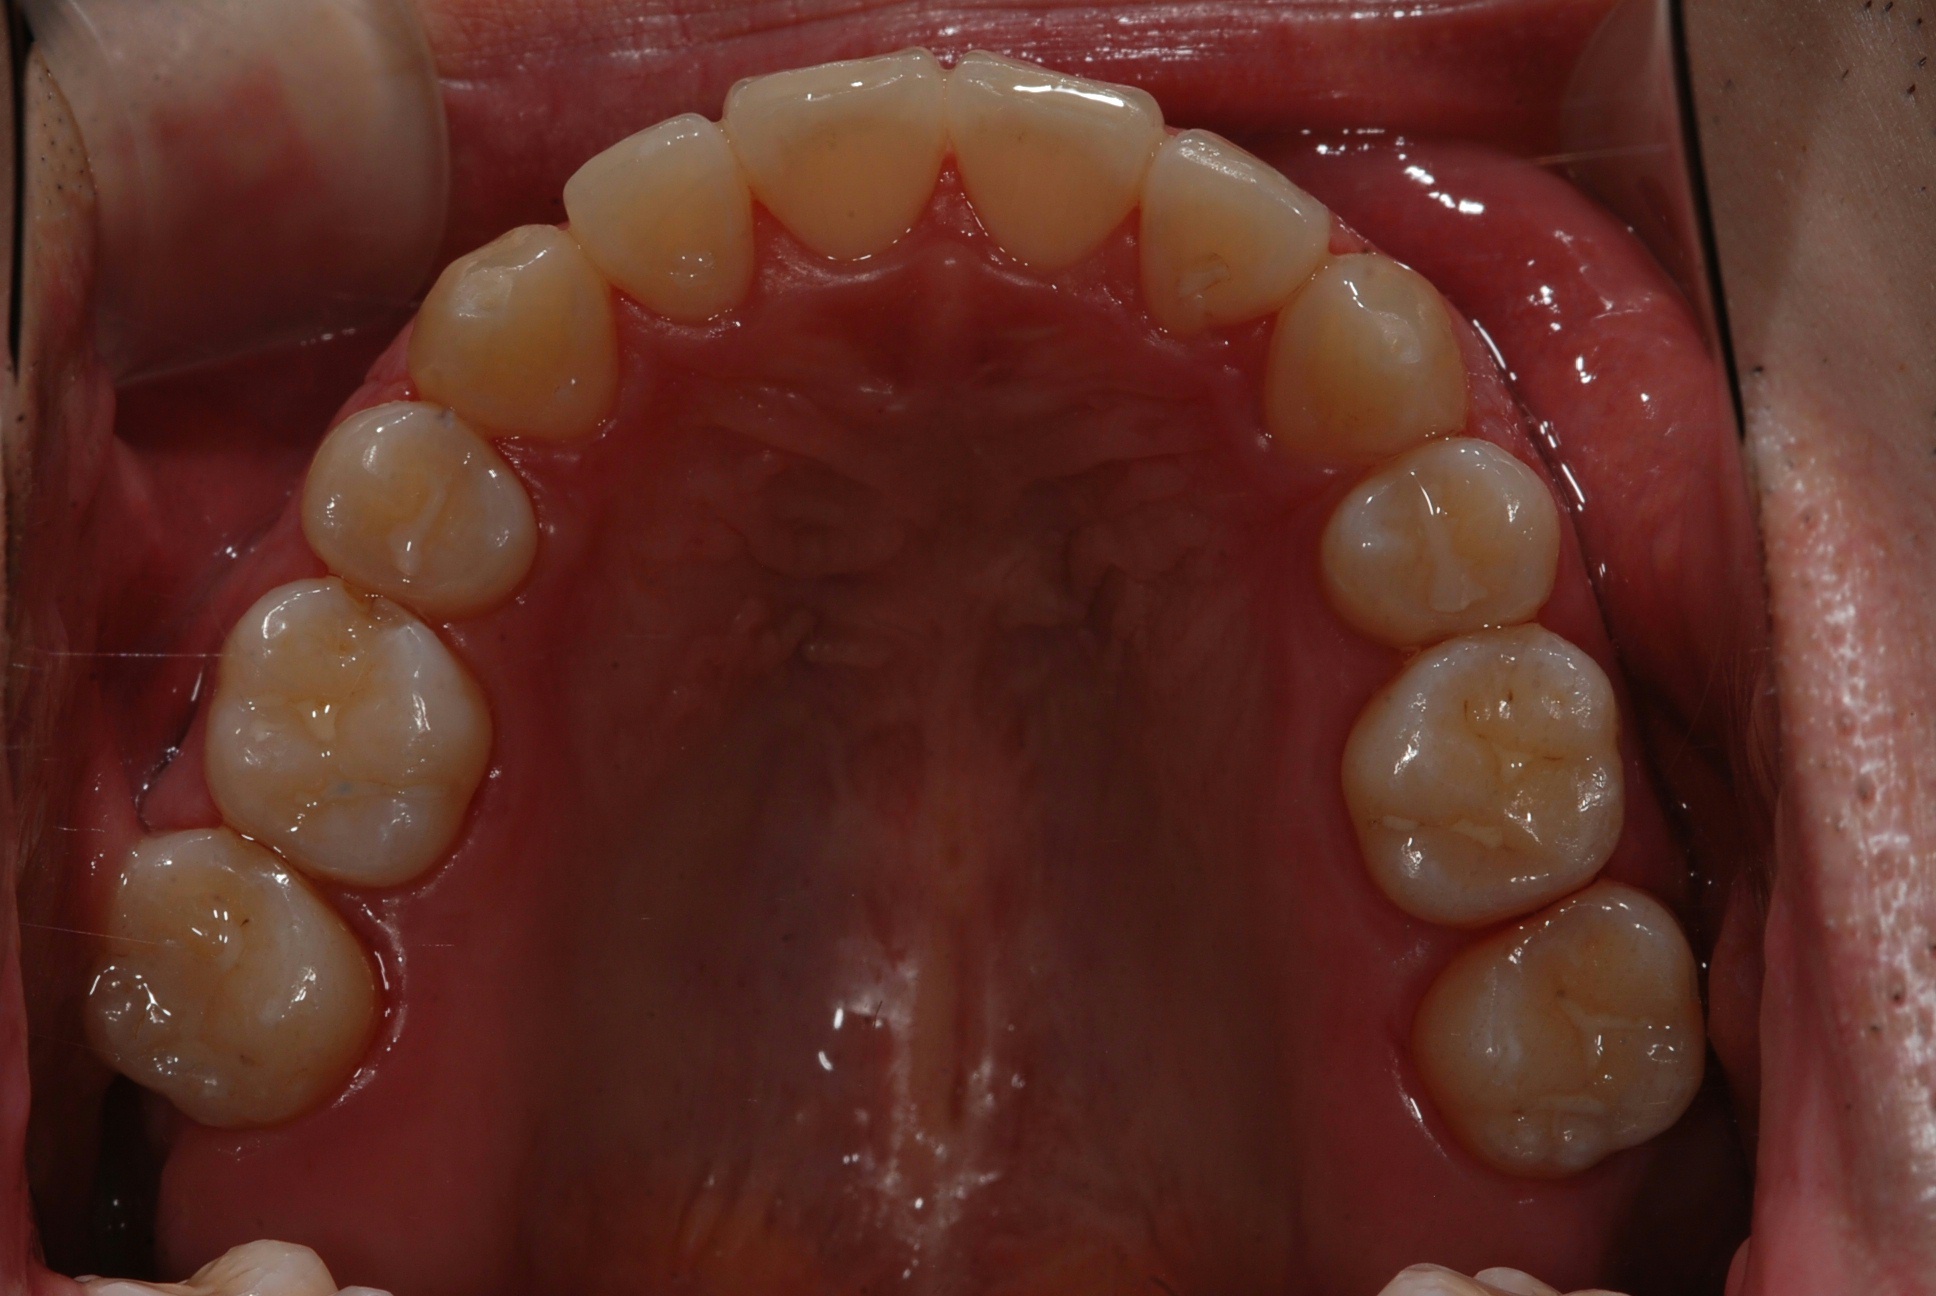

치료 후 사진입니다.